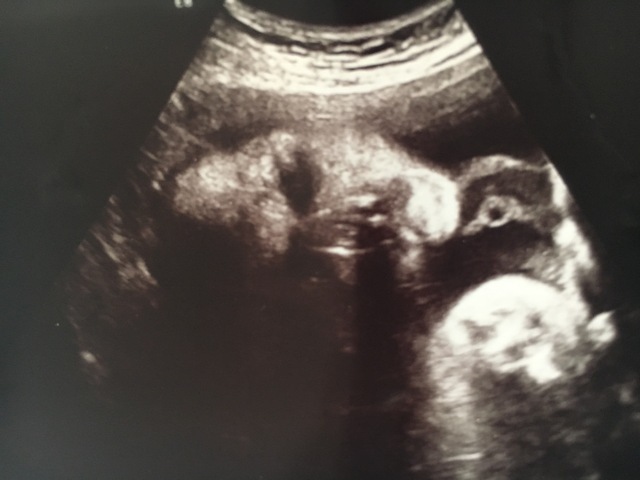

31週2日(31w2d・女の子)|mkmkmkmk さん(23歳)

エコー写真撮影時のエピソード:

初めて背中のエコーを撮ってもらった時はなんて綺麗な背骨!って大はしゃぎしてたけど4週連続背中のエコー...

背中はもういいから顔を見せておくれ(笑)